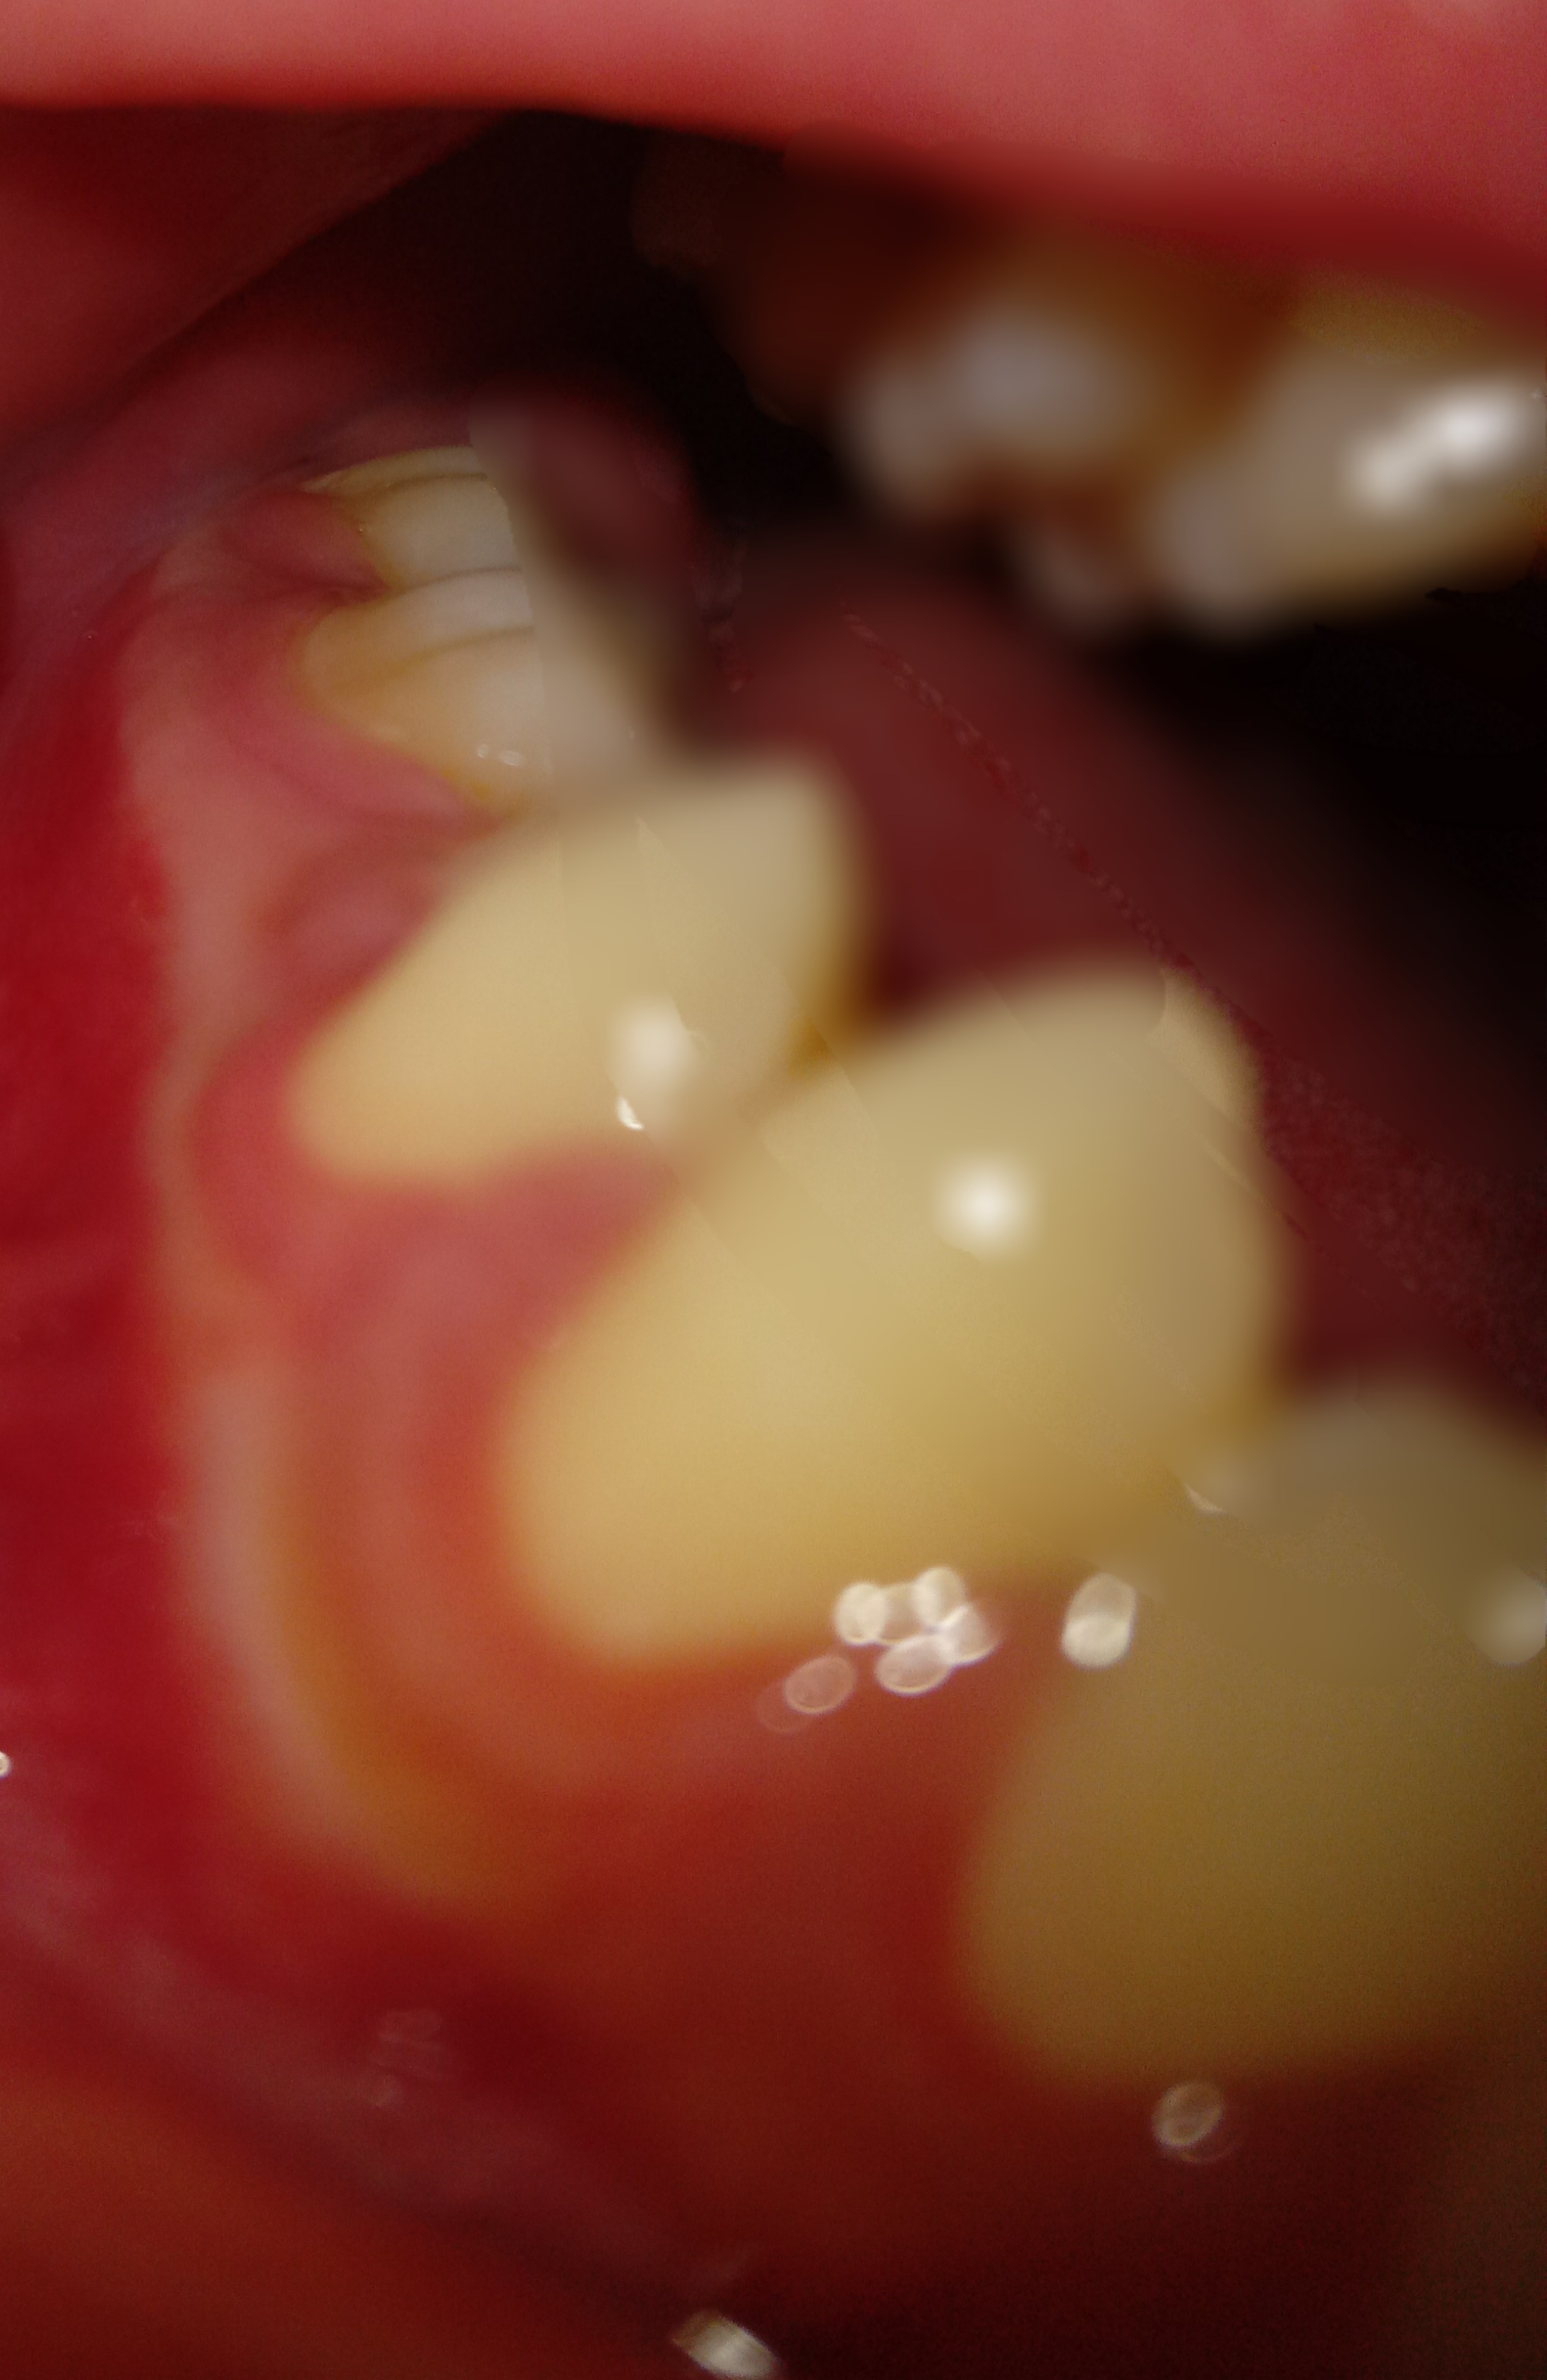

Em có nhổ răng khôn vào hồi t2.Sau 1th thì gần vị trí răng khôn đã nhổ có xuất hiện 1 nốt phồng ,khi ấn vào thì thấy có dịch màu ngà vàng chảy ra.Em cs súc miệng nc muôia thì có thấy nốt đó teo dần.Nhưng hôm sau cx ở vị trí răng khôn cs 1 nốt nhỏ mọc lên nốt này thì lại cứng,nhỏ.Với tình trạng lợi của e dạo này rất mỏng,có thể thấy đc luôn cả xương or hàm răng.Kbt đây là tình trạng gì nhờ bác sĩ giải đâp ạ.

Cái nốt phồng trong ảnh bây h bé lại rồi nm lại mọc 1 nốt mới ở gần đó nốt này cứng và chắc hơn nốt phồng này( nốt phồg này mềm ko đau ko cứng có dịch ngà vàng) thì bị sao ah